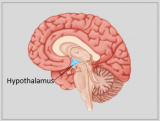

A neuroanatomia é o ramo da anatomia que estuda a anatomia do sistema nervoso, ou seja, a estrutura, a função e a organização do sistema nervoso. O sistema nervoso é um dos sistemas mais complexos do corpo humano e inclui o cérebro, a espinal medula, os nervos periféricos e os gânglios nervosos. A neuroanatomia preocupa-se com a forma como estas estruturas estão ligadas entre si, como os sinais são transmitidos entre as células nervosas e como as diferentes partes do sistema nervoso trabalham em conjunto para controlar as funções corporais e cognitivas. Os neuroanatomistas utilizam técnicas de imagiologia avançadas, como a ressonância magnética (MRI), a tomografia por emissão de positrões (PET) e a microscopia para visualizar as estruturas e funções do sistema nervoso.